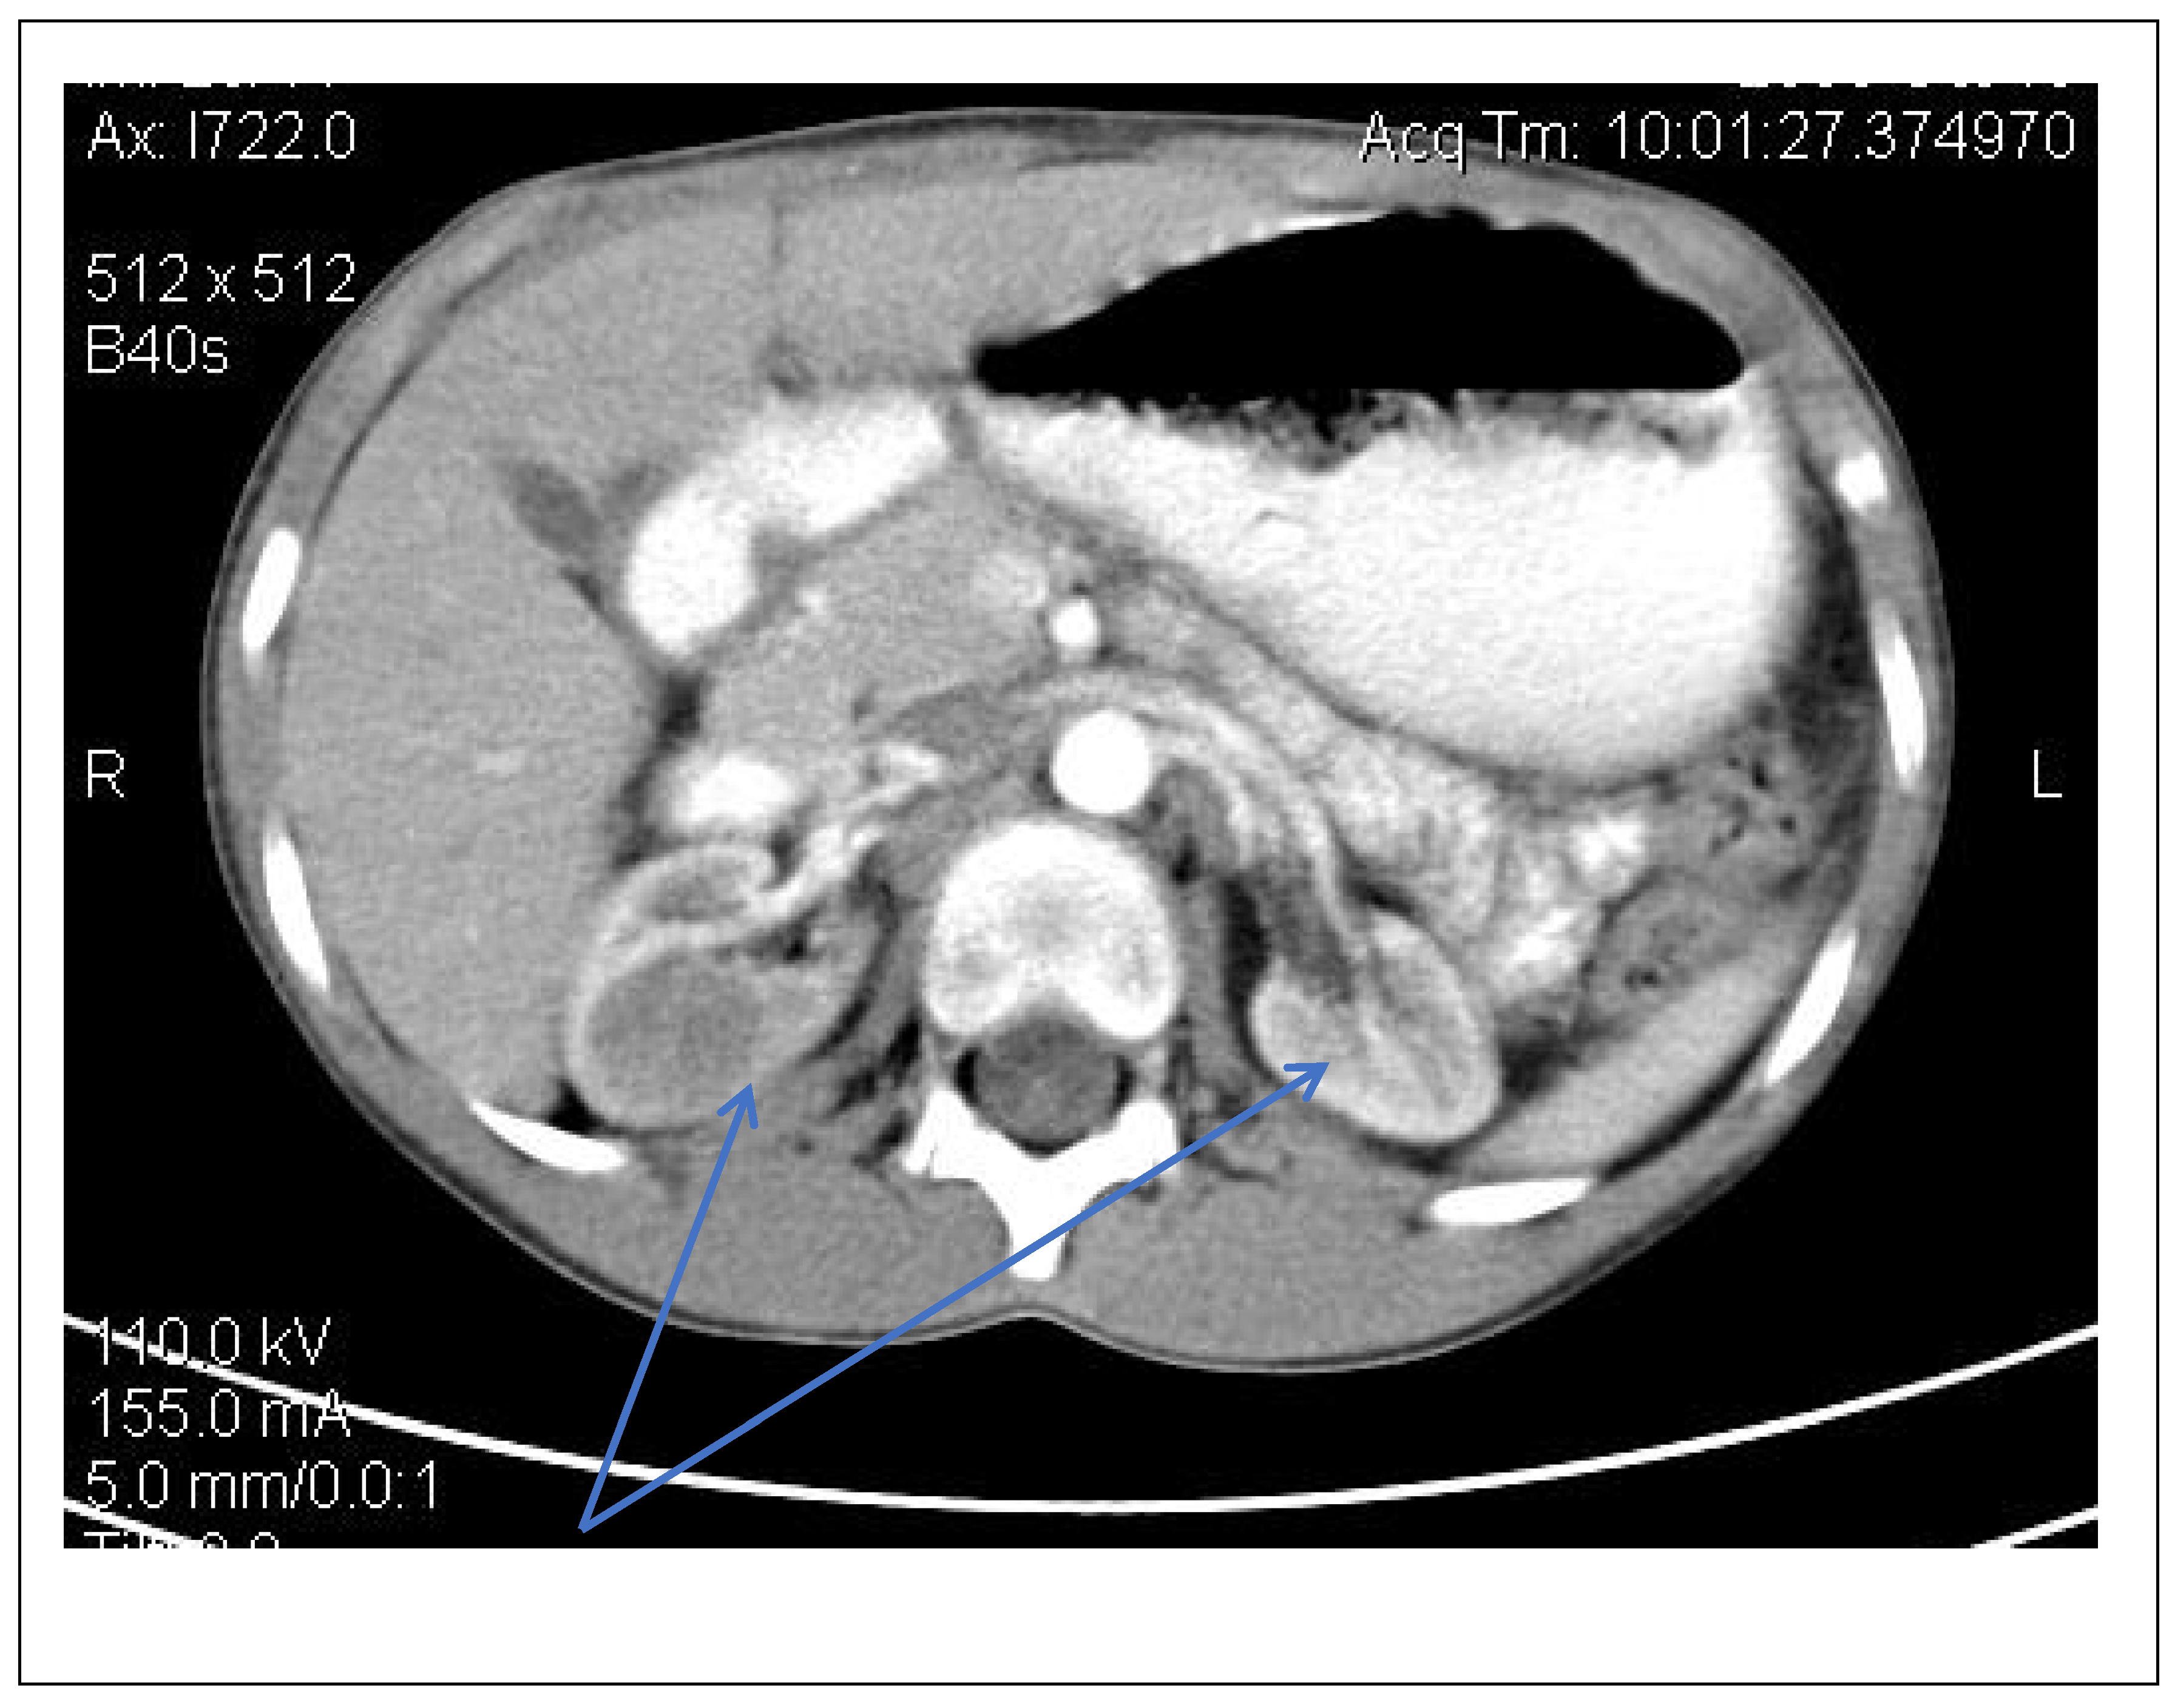

Enzyme replacement therapy (ERT) (Agalsidase β) was subsequently initiated, under which the patient showed a favorable evolution, with the disappearance of palmo-plantar burning acroparesthesias after 3 months of therapy, the normalization of the echocardiographic appearance and the disappearance of left ventricular hypertrophy after 6 months and the disappearance of renal hyperechoic formations on CT-scan after 12 months (Figure 13). Enzyme activity was also tested on the mother and the sister, the mother showing α-galactosidase deficiency.

Figure 13. Abdominal CT scan—disappearance of renal hyperechoic formations (blue arrow).